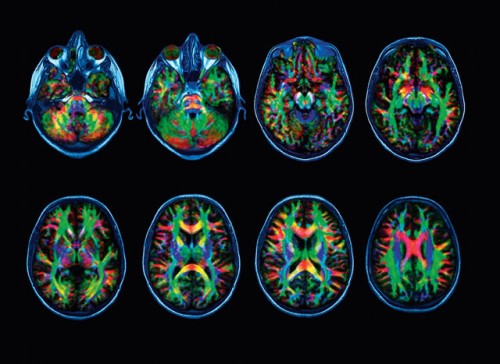

Onze hersenen maken voortdurend verbindingen tussen verschillende hersendelen. Dat is complex en vraagt van ons denken heel wat energie.

Om het leefbaar te houden gebruiken we in gelijkaardige situaties dezefde verbinding. En een volgende keer weer. Zo ontstaan routines en wordt een verbinding steeds dikker en krachtiger. Gevolg? Het wordt nog aantrekkelijker om iets op dezelfde manier te doen.